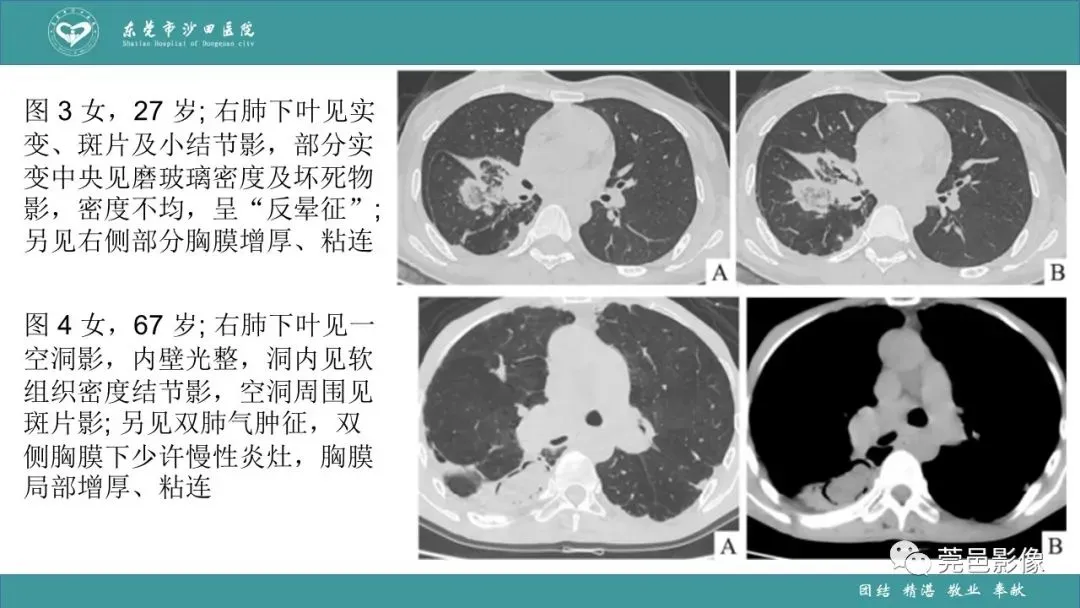

>课件 | 肺炎克雷伯杆菌肺炎影像学诊断与鉴别诊断

课件 | 肺炎克雷伯杆菌肺炎影像学诊断与鉴别诊断